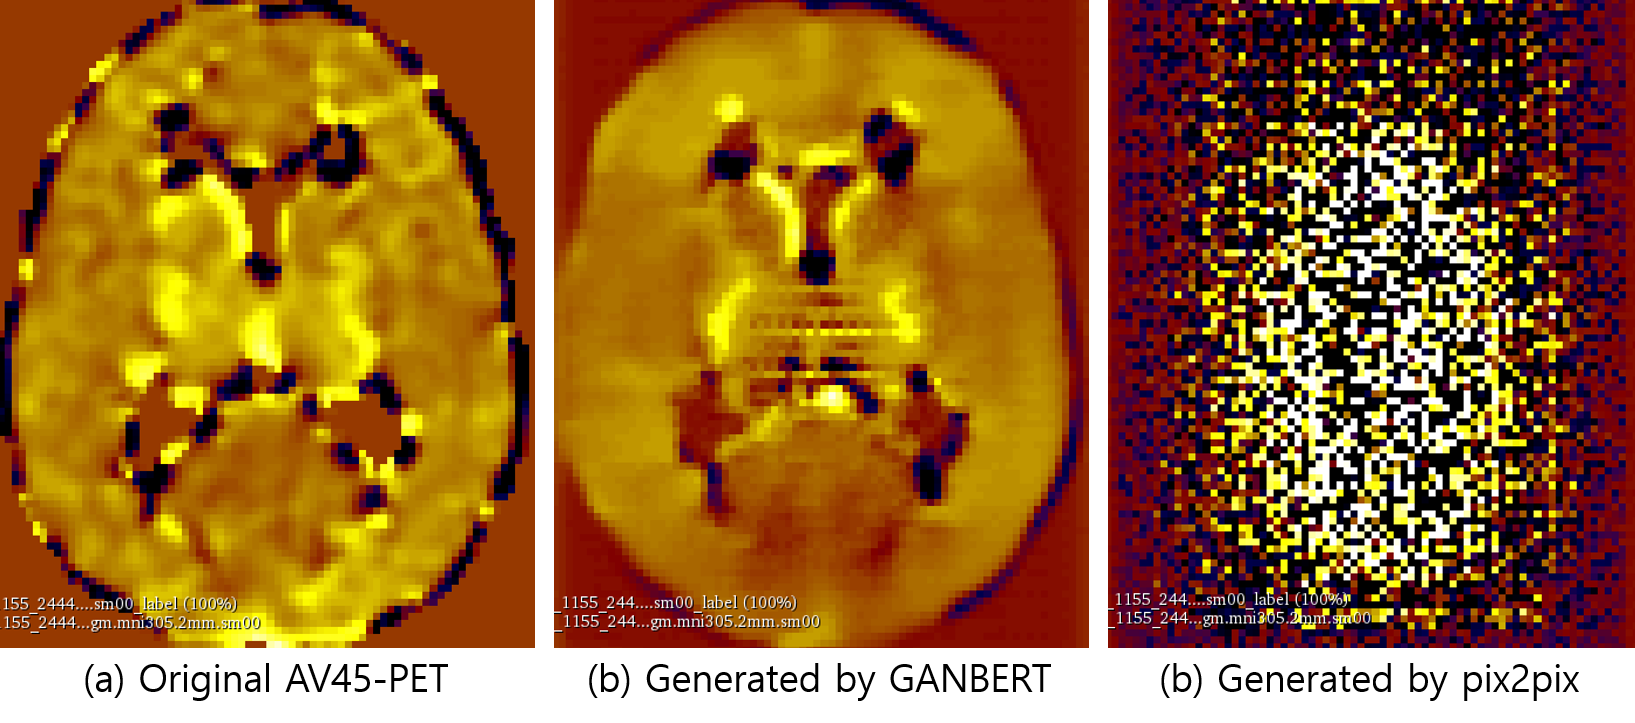

Refer to caption

Figure 4: AV45-PET (a) original; synthesized by (b) GANBERT; and (c) 3D-pix2pix.

5.2 Visual Examples of Generated PET Images

Examples of AV45-PET images generated by GANBERT and pix2pix are compared with the original PET image in Figure 1. GANBERT manages to generate close to the original AV45-PET image while pix2pix fails to generate a reasonable image. Some more examples of AV1451- and FDG- PET images generated by GANBERT are compared with the original PET images in Figure 2. Overall, images to close to the original PET images are generated by GANBERT in all three PET imaging techniques tested. The image quality of the center of the brain region is not as good as the other region, and it is suspected due to (1) differences in MRI and PET images, and (2) lack of training data.